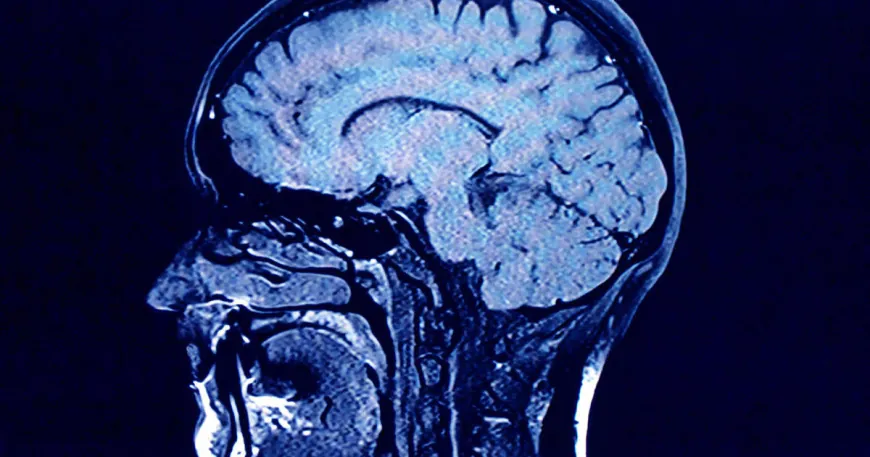

Study finds growing levels of microplastics in human brains

Human brains contain higher concentrations of microplastics than other organs, according to a new study, and the amount appears to be increasing over time.